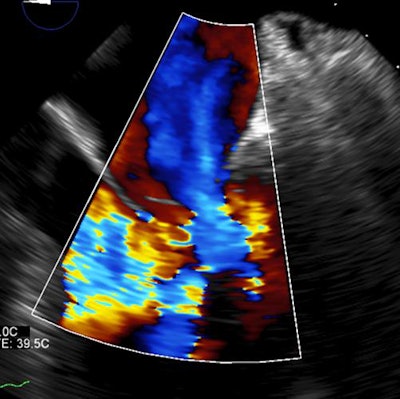

- Cardiac: Known heart disease, valvulopathy, amiodarone